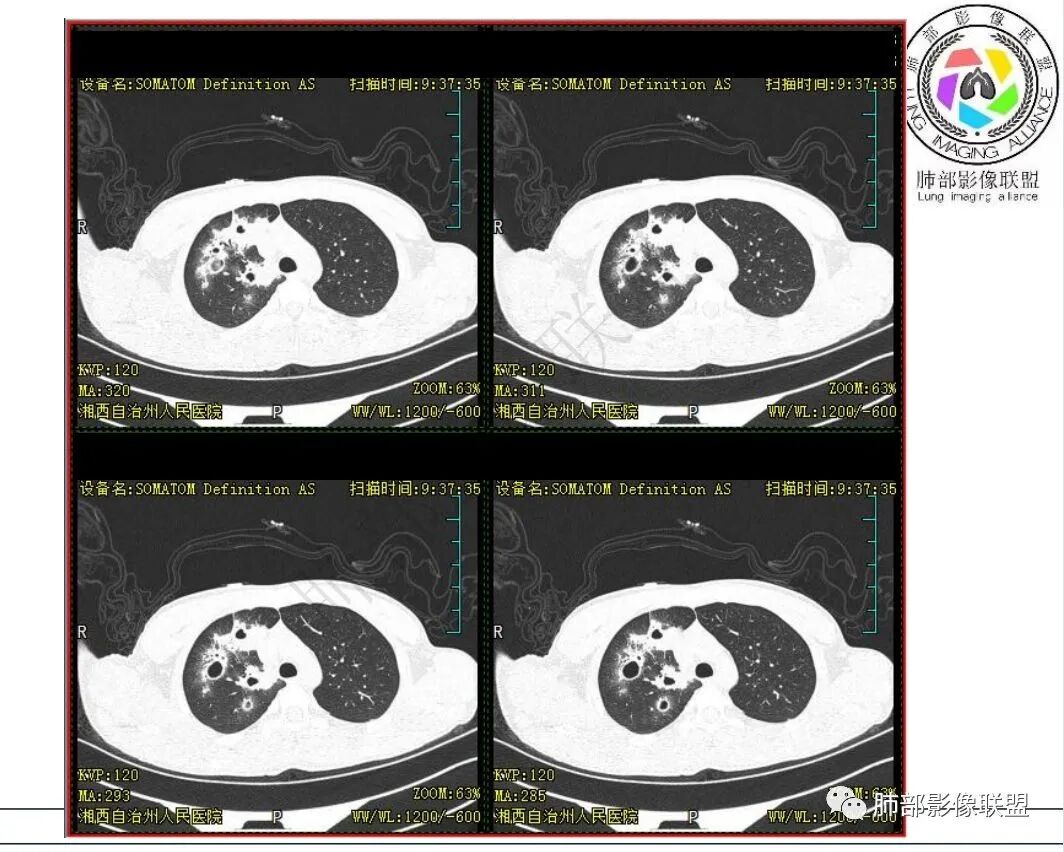

青少年男性,右肺多发斑片状实变影、结节影,长轴平行于胸膜,边缘收缩、模糊,另可见薄壁空洞,内壁光整,边缘模糊,考虑结核合并隐球菌

儿童,右肺多发散在斑片影,结节,实变,边缘凹陷,可见多发空洞样改变,内壁光滑,周边散在磨玻璃样结节,考虑诺卡菌可能,鉴别金葡、血管炎

右肺上叶多发斑片及结节影,边缘凹陷,可见多发空洞,内壁光滑,周边磨玻璃样改变,常规考虑结核,但临床不支持,考虑,寄生虫?努卡?鉴别隐球菌

青少年,呼吸道症状,急性病程。有结核病患接触史。血沉增高,淋巴细胞稍低。胸部CT:右肺上叶多发结节并空洞,洞内干净,洞壁内缘光整,边界模糊,周围晕,边缘收缩,部分病灶侧向融合,定位气道来源病变。考虑感染性病变,疾病谱:NTM,TB、努卡、金葡。

上叶多发空洞,有晕,局部沿支气管血管束走行,咳血,年轻男性,树芽征不明显,淋巴结肿大不明显,临床结核指标不支持,首先考虑ntm,鉴别结核,奴卡,曲菌,血管炎,马尼

从发病部位,实变病灶的边缘、密度,空洞的特点,支持慢性炎性病变,结核首选